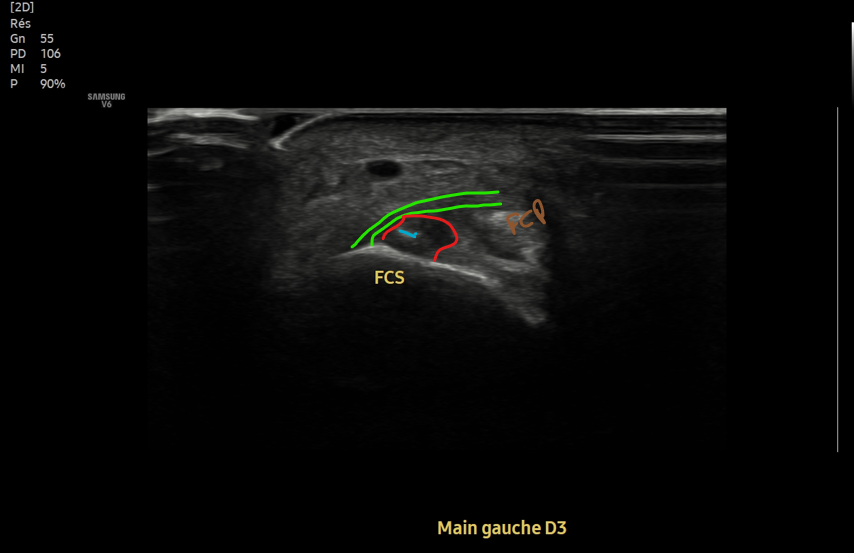

@BordesJeremie Si la lésion n'est pas trop grave on peut assez vite regrimper dessus avec une syndactylie

Français

@BordesJeremie Syndactylie entre les deux doigts concernés (3/4 pour le 3e, 4/5 pour le 4e), puis kiné faite par quelqu'un qui connait l'escalade. En gros on va remettre en charge en isolant progressivement le 4e doigt